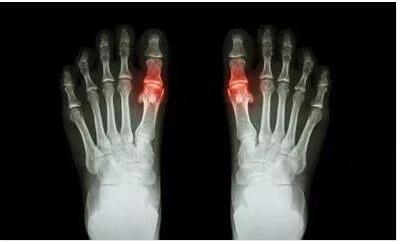

生活中痛风患者越来越频繁,大家对痛风也往往是无可奈何,不知道 ...

随着社会的发展,人们生活方式的改变,痛风的患者也越来越多。痛 ...

慢性痛风性关节炎是痛风吗?痛风由于遗传、饮食、性别等等因素而 ...